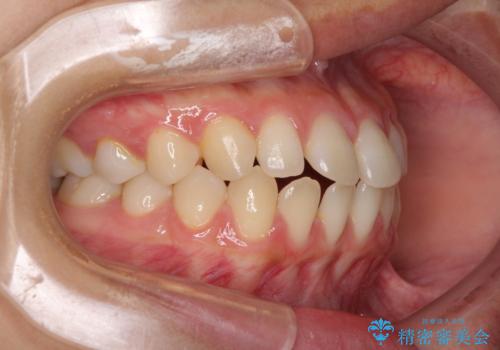

隙間だらけの歯列 インビザラインで改善

- 前歯の上下スペースと前歯の隙間を気にして来院された患者様です。

飲み込みや話をするときに舌を突出させる癖が強くあり、それが原因でスペースが空いていました。

舌癖を改善するためのトレーニングを行いながら、インビザラインにより上下の前歯の隙間を閉じていくこととしました。

空隙歯列(すきっ歯)は、舌の突出癖をある程度改善できたとしても、後戻りにより隙間が開きやすいと言われています。

裏側から細いワイヤーで保定するとともに、睡眠時のマウスピース装着を徹底していただくことで、後戻りを最小限にとどめます。